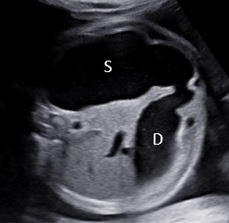

Fetus in Fetu (FIF) là bất thường rất hiếm gặp của song thai một trứng, trong đó một thai không trưởng thành sống ký sinh trong cơ thể của thai bình thường